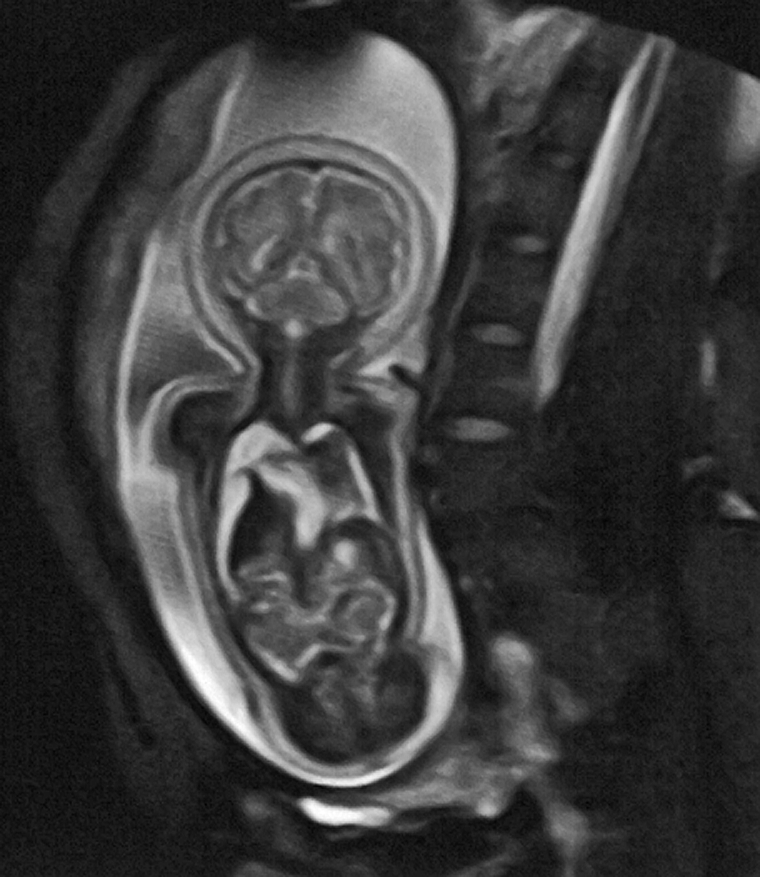

MR imaging is used for fetography (Figure 18-07), particularly for imaging the brain. At 3.0 Tesla (or higher magnetic fields), the specific ab­sorp­tion rate (SAR) and the increased noise may, at least potentially, adversely affect the fetus [⇒ Cannie 2016].

Figura 18-07:

MR fetography in the 32nd week of pregnancy.